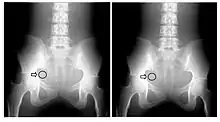

- Contrast-detail evaluation combines physical indices of image quality with observer detection ability. Contrast-detail phantoms contain test objects of different sizes and subject contrast mounted on a plastic plate that is radiographed under specific exposure conditions - see Figure 6.20. Contrast-detail plots are derived on the basis of the borderline visibility of test objects in the image. A disadvantage of this approach however is the introduction of bias as a result of the observer's prior knowledge of the size, shape and location of the low-contrast objects. The link between this type of evaluation and clinical imaging performance is therefore difficult to establish.